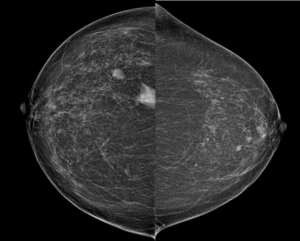

MG showed two high density masses in upper outer quadrant. The smaller one is oval with circumscribed. The larger one has indistinct margins. There are no suspicious calcifications.

MG: Detected often during screening, most commonly as solitary non calcified masses, bilateral in 28%, rarely present with spiculated margins and architectural distortion, ipsilateral lymph nodal involvement in about 40%